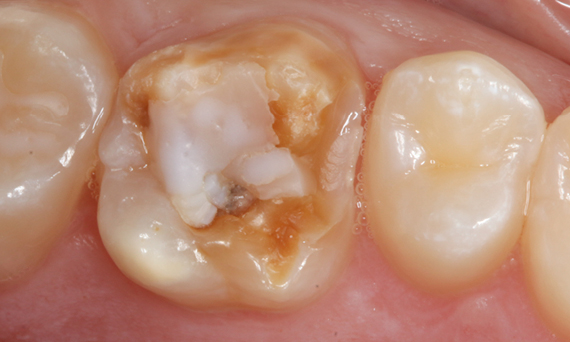

Composite filling, tooth 16, before CEREC treatment

Before

Large insufficiency of the composite filling on tooth 16 with distal marginal ridge cracks, a lingual wall crack and distal recurrent decay.

After

Highly esthetic full-surface glass-ceramic crown.